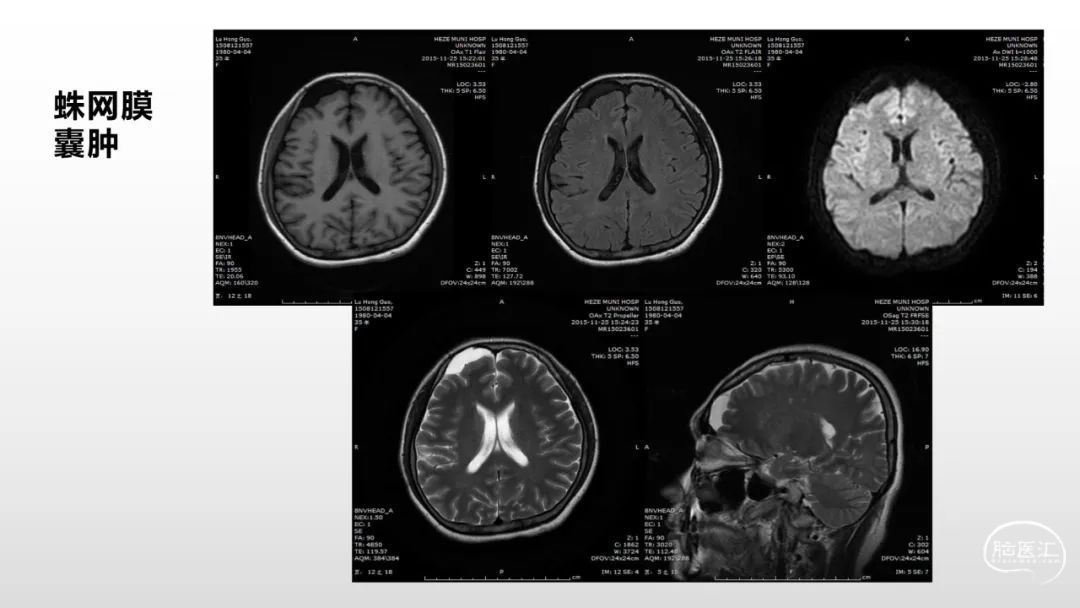

颅脑影像诊断基础知识讲座:脑膜病变

马洪舟

菏泽市立医院